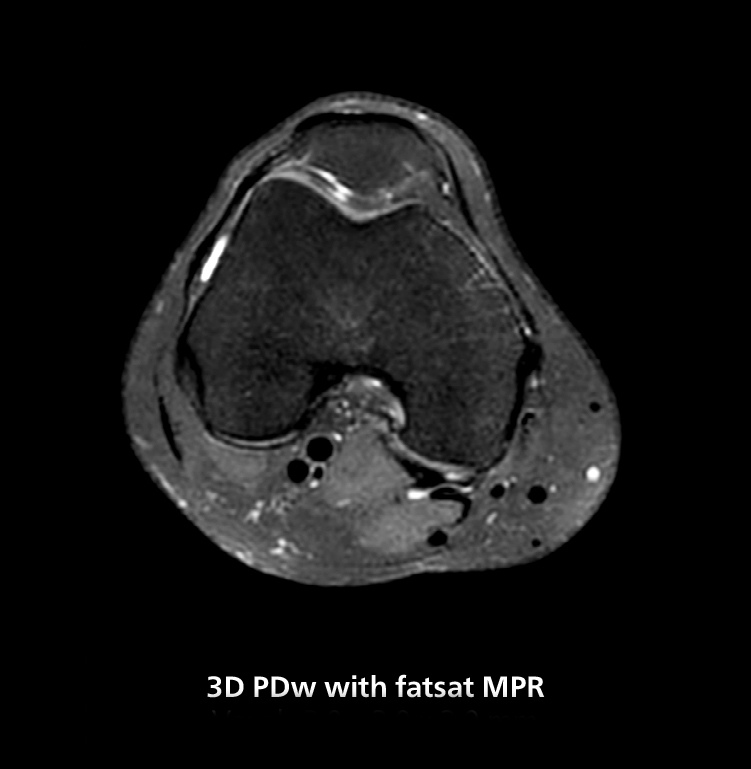

3D knee imaging

The isotropic high resolution 3D sequence in this MRI case allows for reformatting to obtain other orientations with high quality. Acquired on the MR 5300 system.